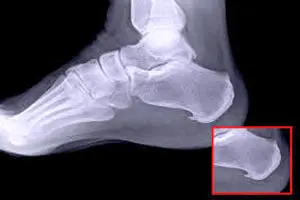

خار پاشنه یا خار استخوانی، زائده‌ای استخوانی است که از پایین پاشنه پا، جایی که استخوان پاشنه به رباط بین پاشنه و قسمت برجسته پا (فاسیا یا نیام کف پا) متصل می‌شود، بیرون می‌زند. خار پاشنه به مرور زمان ایجاد می‌شود. اکثر افراد تا زمانی که برای درد پاشنه به پزشک مراجعه نکنند، متوجه وجود خار پاشنه خود نمی‌شوند. در حالی که خار پاشنه را می‌توان با جراحی برداشت، پزشکان اغلب درمان‌های غیرجراحی را برای کاهش علائم آن توصیه می‌کنند. خار پاشنه چه ارتباطی با التهاب نیام کف‌پایی دارد؟